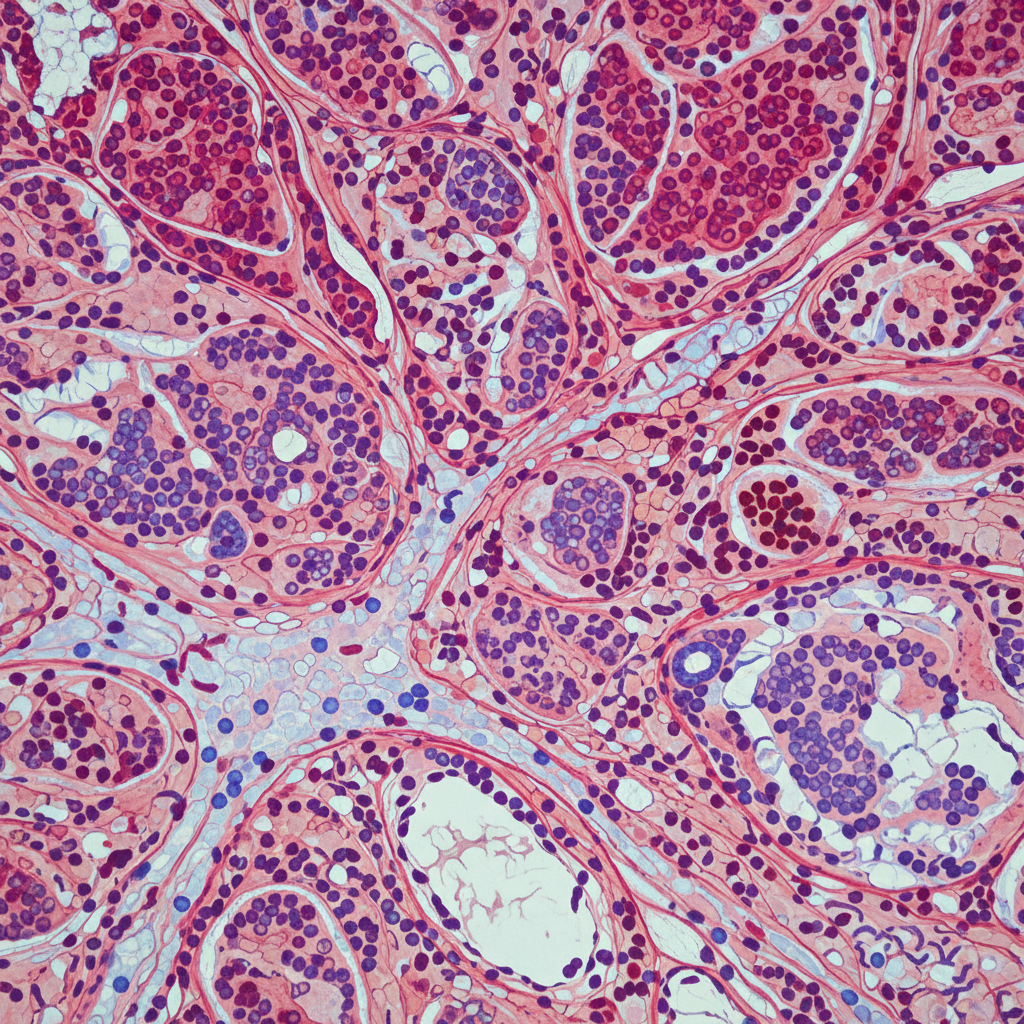

또 다른 질환으로는 **'급성 신우신염'**이 있습니다. 이는 세균이 요도를 타고 올라가 신장까지 감염시킨 상태를 말해요. 옆구리를 가볍게 주먹으로 툭툭 쳤을 때 깜짝 놀랄 정도의 울림 통증이 느껴진다면 급성 신우신염일 확률이 높습니다. 이 경우에는 39도 이상의 고열과 오한이 동반되는 경우가 많으니 꼭 체온을 확인해 보셔야 합니다.